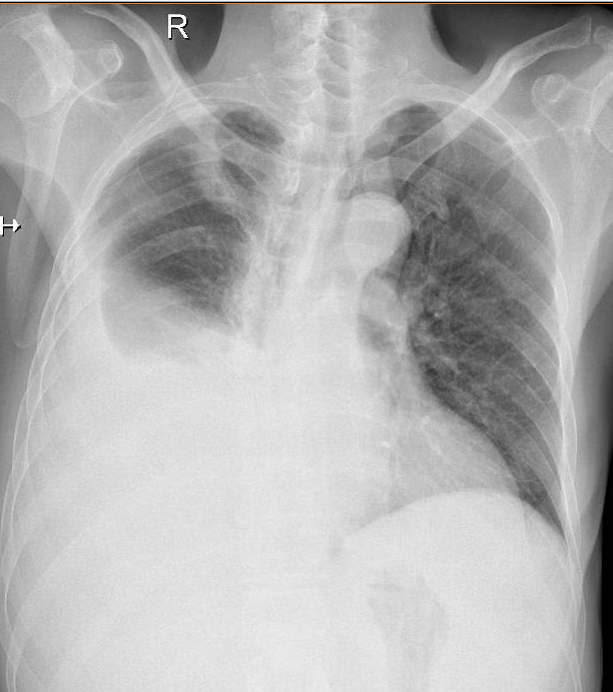

1-Khí quản lệch(T) 2- Dải xơ thùy trên phổi (P) 3-Tràn dịch màng phổi (P) lượng nhiều 4-Vẹo cột sống ngực sang (P) 5-Tật bẩm sinh dính cung trước (T) xương sườn 1-2